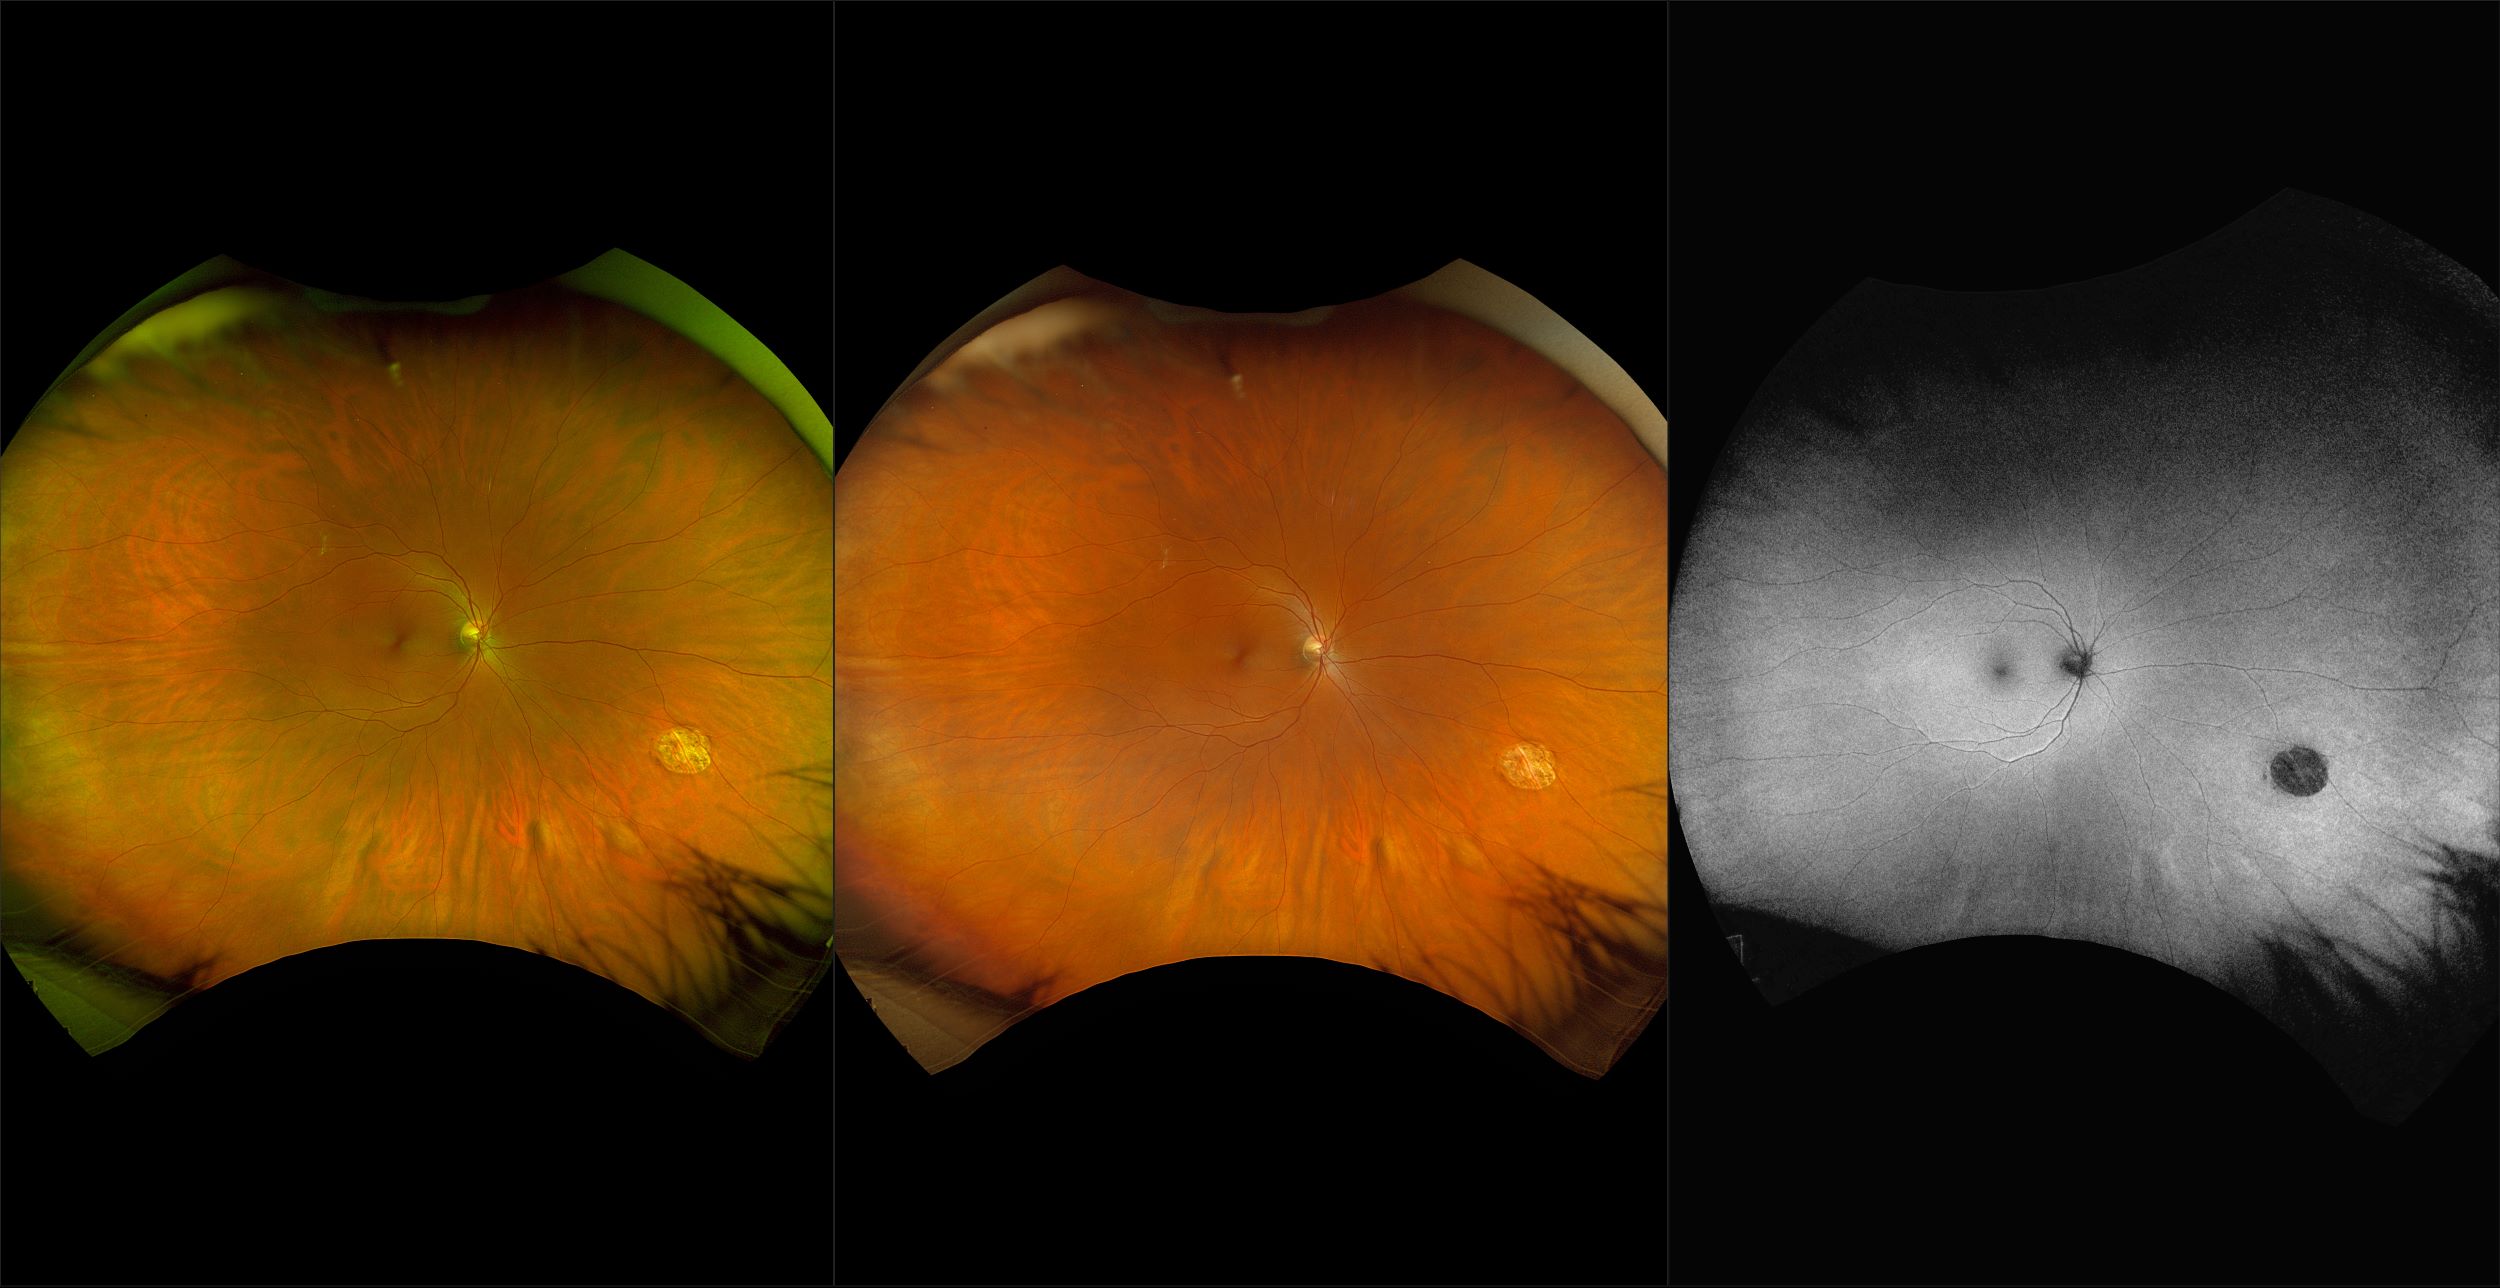

California - Large Pars Plana Cysts - Steered, RG

Pars plana cysts are a common peripheral retinal pathology that do not raise much clinical concern. They do not affect the central vision and observation alone is typically recommended. Pars plana cysts are something to be considered when peripheral retinal elevation is noted on routine exam.